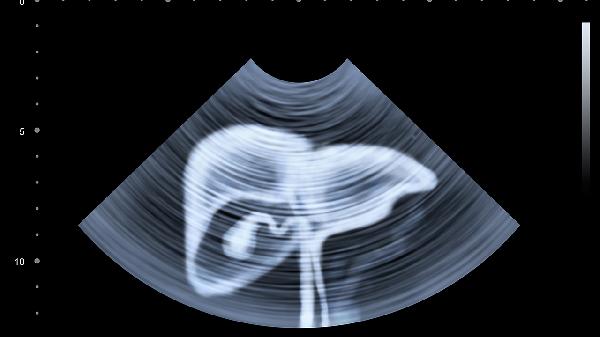

肝脏的代偿能力超乎想象,等出现明显症状时,其功能可能已丧失70%以上。建议有乙肝、脂肪肝等基础肝病的人群,每6个月做一次腹部超声联合甲胎蛋白检查。记住,早期肝癌的五年生存率可达70%以上,关键就在于及时发现这些蛛丝马迹。从今天开始,学会倾听身体发出的微弱信号,别让"沉默的杀手"有机可乘!